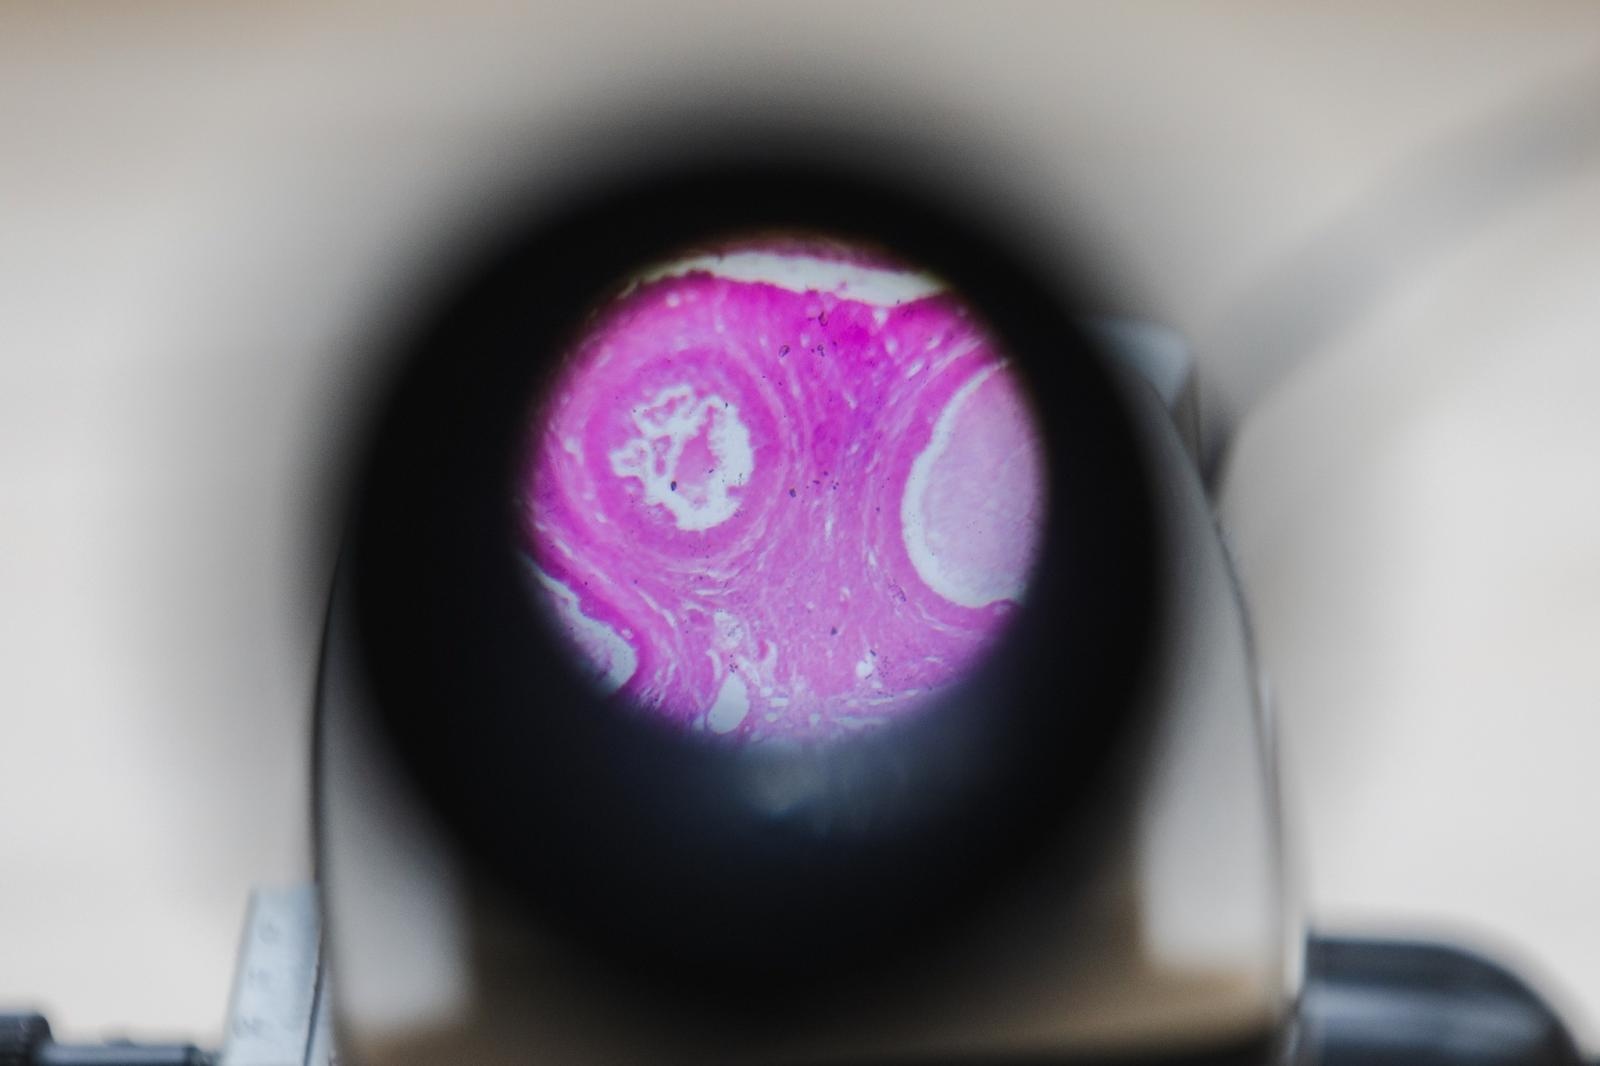

Dzięki przyznanym środkom Zielona Pracownia przeszła kompleksową modernizację. Zakupiono nowe meble, w tym ławki, krzesła i specjalistyczny stół laboratoryjny. Pracownia została również wyposażona w nowoczesne pomoce dydaktyczne, multimedia oraz sprzęt, który umożliwia uczniom praktyczne zgłębianie wiedzy z zakresu ekologii, biologii, ochrony środowiska oraz nauk przyrodniczych.